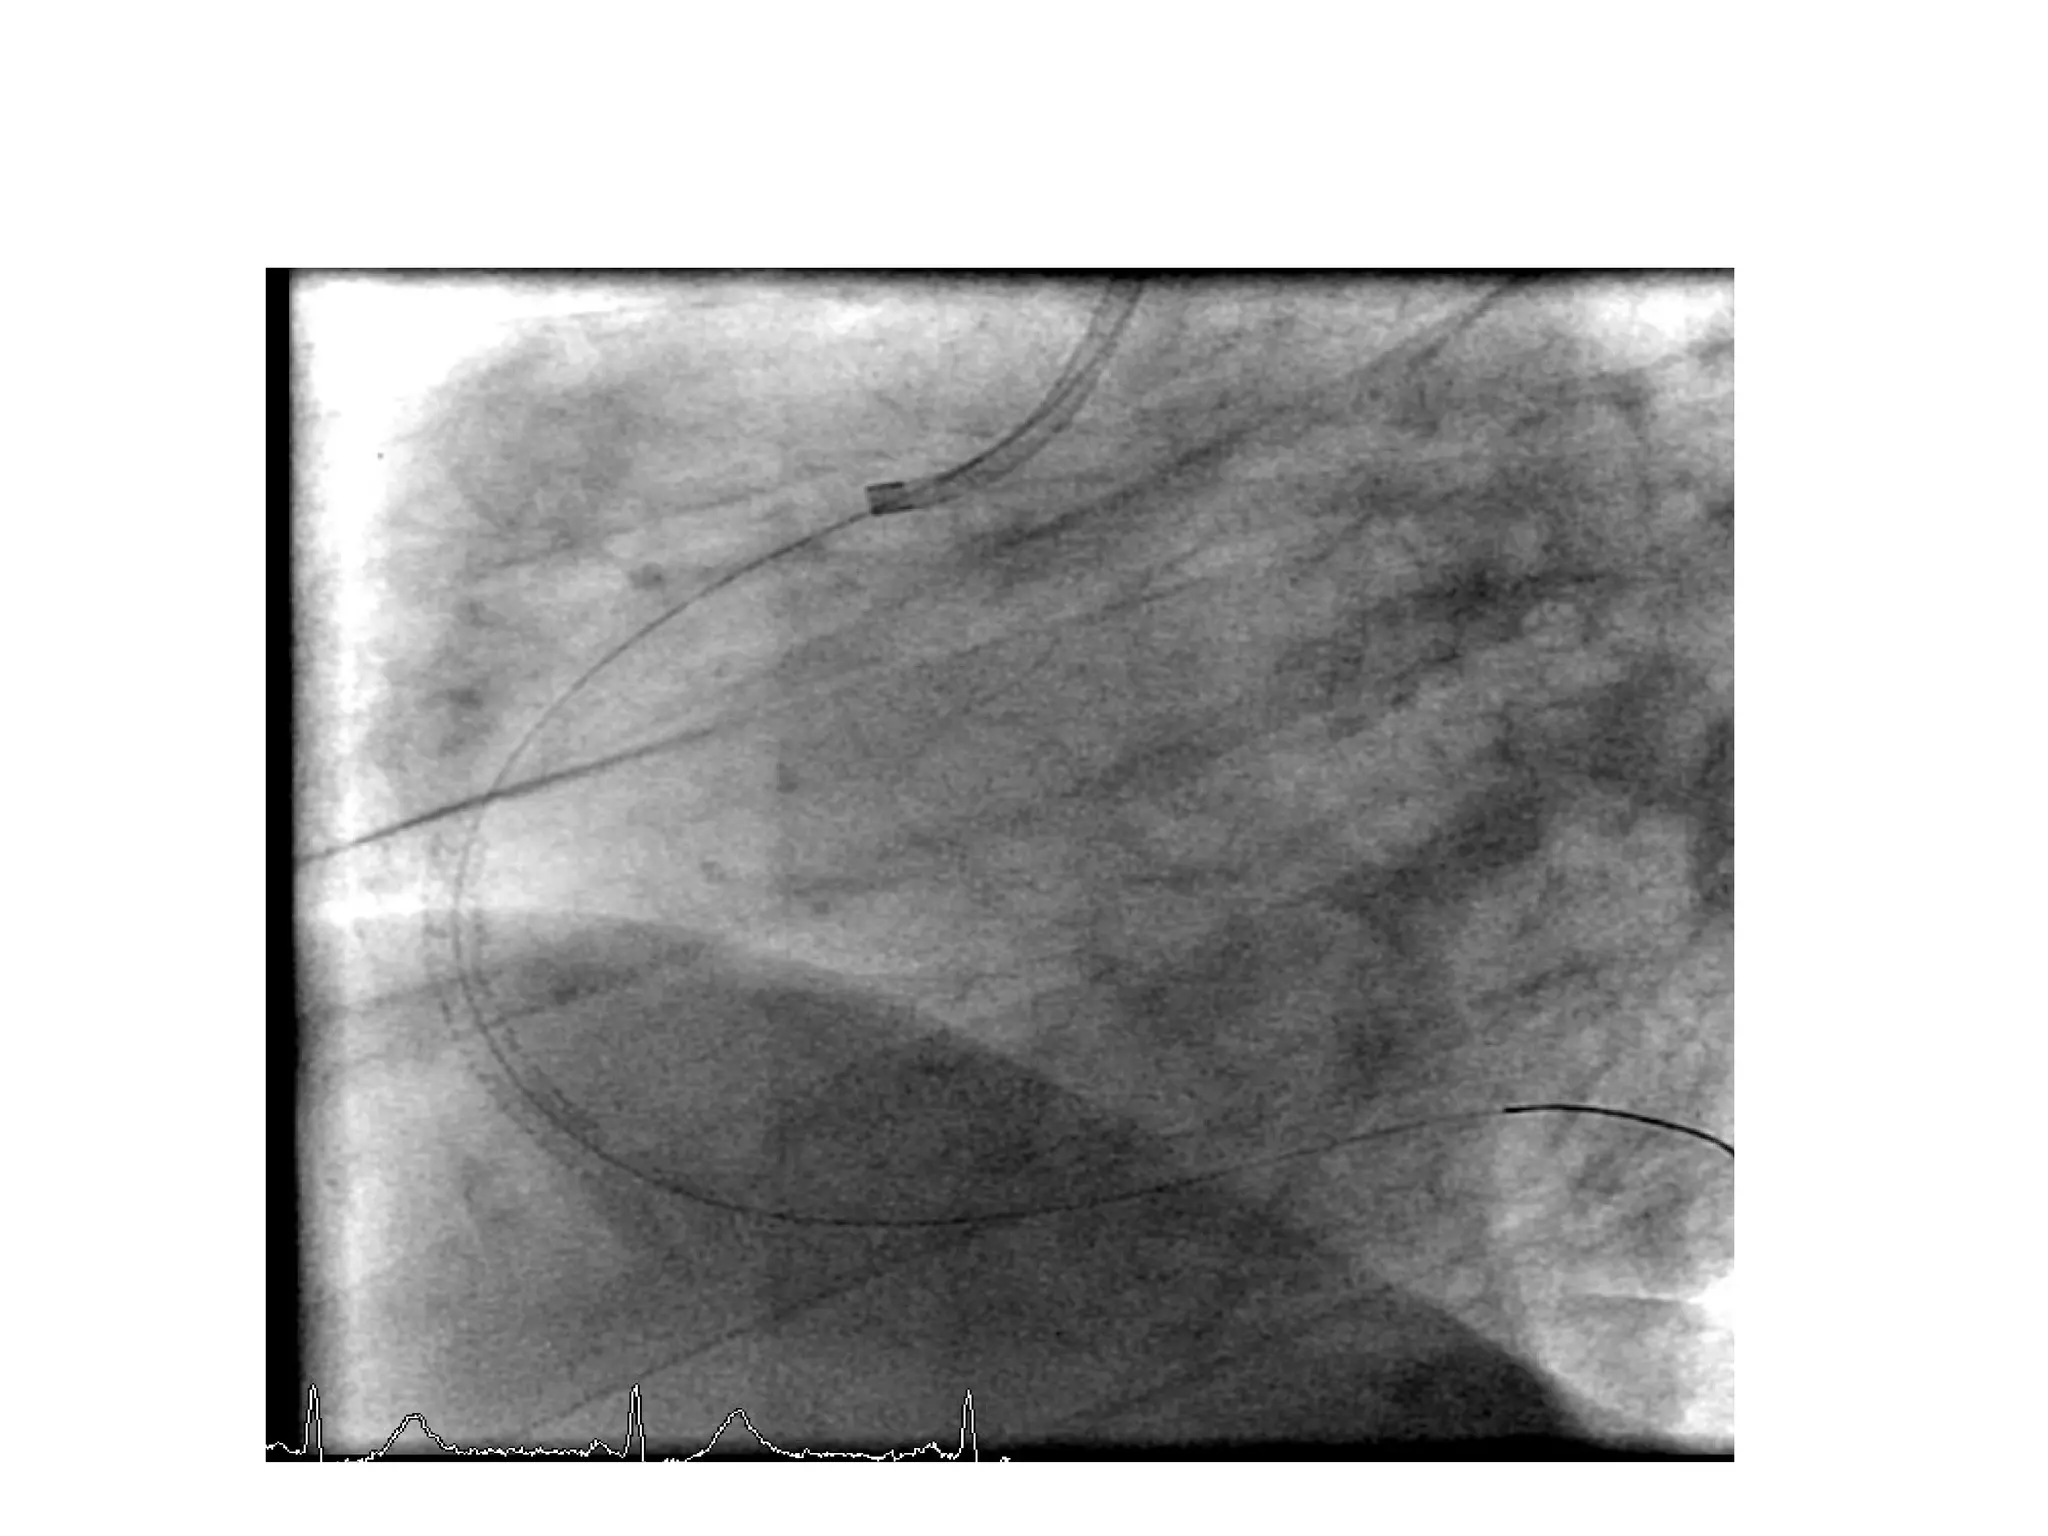

A 43-year-old man presented with chest pain and was diagnosed with an acute inferior ST elevation myocardial infarction with evidence of right coronary artery occlusion but no right ventricular involvement; he underwent primary percutaneous coronary intervention of the mid right coronary artery, which had a clot. The same patient had a complex lesion in the left anterior descending artery and its diagonals requiring staged percutaneous coronary intervention. A 55-year-old woman with diabetes and chest pain was found to have severe reversible ischemia in the territories of the left anterior descending artery and right coronary artery on nuclear stress testing, with normal circumflex artery area; coronary angiography revealed a critical proximal lesion in the left anterior descending artery.